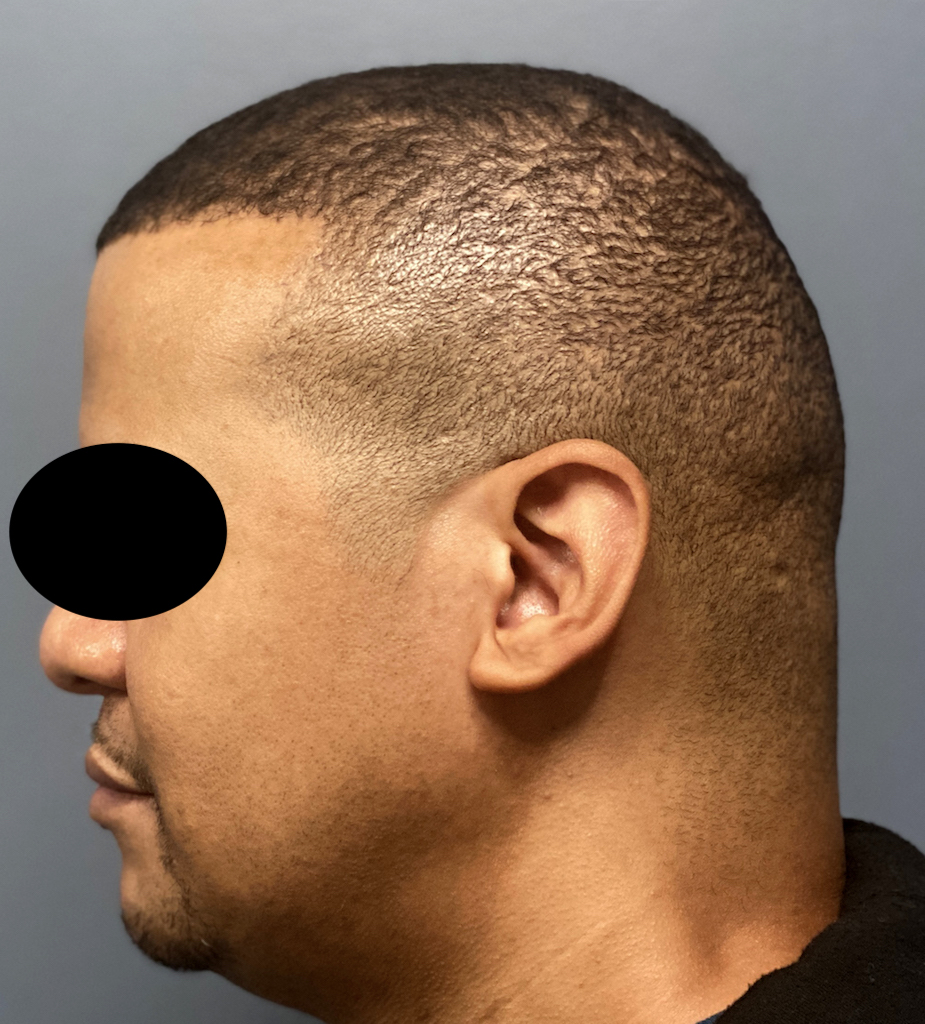

Desire for reshaping of an asymmetric flat back of the head in a shaved head male.

A combined back of the head reshaping procedure was done with a custom skull implant, sagittal ridge reduction and a right temporal muscle reduction.

Desire for reshaping of an asymmetric flat back of the head in a shaved head male.

A combined back of the head reshaping procedure was done with a custom skull implant, sagittal ridge reduction and a right temporal muscle reduction.